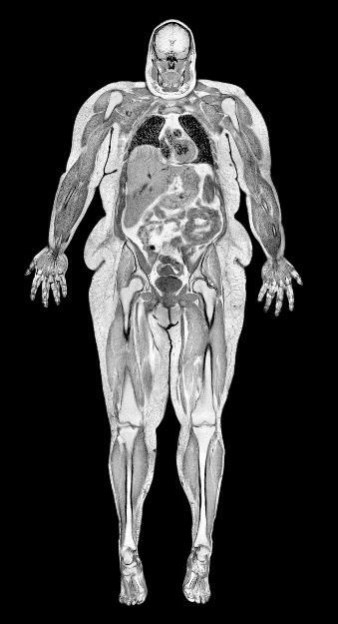

Гиподерма Термин «гиподерма» происходит от греческих слов, означающих «под кожей». Гиподерму часто называют подкожно-жировым слоем или подкожной фасцией. Технически гиподерма не является частью кожи, но она соединяет кожу с остальной частью тела и сливается с соединительными тканями, покрывающими мышцы. Гиподерма, которая состоит в основном из белой жировой ткани (подкожно-жировой клетчатки), кровеносных сосудов и белковых волокон, выполняет сразу несколько функций: • коллагеновые волокна гиподермы позволяют коже без труда перемещаться по низлежащей мышечной ткани; • большое содержание жира в гиподерме служит теплоизолятором, амортизатором и резервным запасом энергии; • жировая ткань является основным эндокринным органом, секретирующим гормоны. Она выделяет небольшое количество эстрогена (у мужчин и женщин), а также гормон лептин, который управляет чувством голода. Гиподерма содержит рецепторы, позволяющие ей реагировать на сигналы других эндокринных органов и нервной системы. Типы жировой ткани Около 50 % гиподермы здорового взрослого человека состоит из жира. Этот тип называют белой жировой тканью, она накапливается в организме, когда вы набираете вес. Бурый жир, также известный как бурая жировая ткань, располагается в передней и задней частях шеи и в верхней части спины. В бурых жировых клетках много митохондрий, а железо, содержащееся в этих митохондриях, придает клеткам бурый оттенок. Наше тело использует бурый жир только для сжигания калорий и выработки тепла. В отличие от белой жировой ткани, бурый жир не откладывается про запас, а физические упражнения, сон и воздействие холодных температур, наоборот, увеличивают количество такого жира в организме. ![]() Висцеральный жир при метаболическом синдроме. Это серьезная патология, при которой вокруг органов скапливается большое количество белой жировой ткани. Увядание кожи Одним из преимуществ или недостатков нашей кожи является то, что она наглядно демонстрирует процесс старения. Как правило, возрастные изменения в коже начинаются после тридцати лет. Из-за образа жизни и невоздержанности этот процесс может ускоряться. С возрастом наша кожа теряет свою эластичность: клетки уменьшаются в размерах, а в эпидермисе и дерме увеличивается количество аномалий. Если базальный слой замедляет производство новых клеток и не поспевает за скоростью отмирания клеток из рогового слоя, то эпидермис истончается. С возрастом коллагеновые и эластиновые волокна дермы, обеспечивающие прочную структуру кожи, теряют свою упругость и деформируются, что приводит к образованию морщин. К возрастным изменениям в гиподерме относится потеря жировой ткани, особенно в руках и ногах. Это лишний раз подчеркивает изменения в дерме и способствует обвисанию кожи. А с потерей упругости кровеносные сосуды становятся более уязвимыми к перфорации и ушибам. Разве вы не волосаты? Наши волосы – это еще одна разновидность мертвых клеток эпидермиса. Для многих людей волосы в равной мере повод и для гордости, и для беспокойства. Около 5 миллионов белковых волокон, или филаментов, испещряют поверхность кожи. У большинства людей с густой шевелюрой свыше 100 000 прядей на голове. Волосы выполняют множество функций, включая: • теплоизоляцию; • защиту носа и ушей от попадания вредных микробов; • защиту внутренних структур от солнечных лучей. Этим и объясняется высочайшая плотность волосяного покрова на голове: он защищает ценнейший орган нашего тела – мозг. ![]() Со временем во всех трех слоях кожи происходят изменения. Структура волос Стержень: волосы развиваются так же, как и верхний слой кожи. Видимая часть пряди, или стержень волоса, – это особая форма кератина. Он состоит из трех слоев: губчатого внутреннего ядра (мозгового слоя), среднего – кортекса (коркового вещества) и наружного, прозрачного слоя кутикулы. Все клетки стержня – неживые. Фолликул: стержень удерживается на коже благодаря трубке эпидермальных клеток – волосяному фолликулу, который проникает в дерму. Волосяные фолликулы формируют скрытую часть пряди – корень волоса. Форма волосяных фолликулов определяет тип волос: вьющиеся, прямые или волнистые. ![]() Луковица: если рассмотреть корень волоса повнимательнее, можно увидеть, что он имеет форму луковицы, чем-то напоминающую лук-батун. Луковица – это место, откуда волос растет. Зародышевый слой базальных кератиноцитов постоянно вырабатывает новые клетки, которые выталкивают вышестоящие вверх, подальше от целебных питательных веществ, поставляемых волосяным сосочком. Сосочек – это структура у основания волосяного фолликула, в которой крошечные кровеносные сосуды переносят кровь, кислород и питательные вещества в волосяную луковицу. Базальные клетки луковицы – одни из самых быстро делящихся клеток. В процессе нашего развития их активные профили заставляют эпидермальные клетки погружаться все глубже в дерму для достаточного кровоснабжения. Также здесь присутствуют и меланоциты, которые поставляют меланин в корневые клетки, а затем окрашивают внутреннюю и среднюю области волосяного стержня. Сплетение: обвивает волосяную луковицу. Сплетение – так закручено называют сеть сенсорных нервов, которые помогают нам ощущать движение волос. ![]() От прямых волос до афрокудряшек: тип волос определяется формой волосяных фолликулов. Рост волос Клетки наших волос – одни из самых активных во всем организме, поэтому иногда им нужна передышка. Вот почему наши волосы периодически входят в стадию активного роста или отдыха, а затем выпадают. За свою жизнь каждый волосяной фолликул может пройти этот цикл как минимум 25 раз. ![]() Этот рисунок показывает три фазы роста волос. Максимальная длина волоса определяется тем, как долго он пребывает в стадии анагена. Анаген. Длина активной фазы роста, также известной как анаген, различается у волос, растущих в разных местах. У волос на голове она занимает порядка 2–6 лет. В других участках (брови или ноги) анаген длится недели или месяцы, чем объясняется короткий период жизни этих волос. В ходе анагена различные факторы роста стимулируют волосяные фолликулы к созданию новых клеток. В любой отрезок времени в этой фазе будет находиться около 80 % всех волос. Волосы на голове растут примерно на 1,25 см в месяц. Известно, что повышенный уровень женского гормона эстрогена во время беременности продлевает эту фазу и награждает женщин более густыми и длинными волосами. |